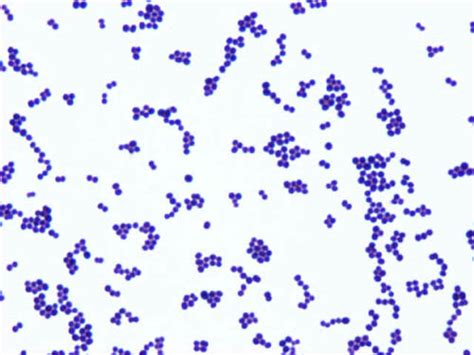

All about #Streptococcal #IE After today's updates in #ECCMID2023 about the inclusion of various Streptococcus species in IE with few exceptions, I decided to compile a few important infographics on Streptococcal IE 1. Streptococcal grouping 2. Incidence of IE #IDTwitter

All about #Streptococcal #IE

After today's updates in #ECCMID2023 about the inclusion of various Streptococcus species in IE with few exceptions, I decided to compile a few important infographics on Streptococcal IE

1. Streptococcal grouping

2. Incidence of IE

#IDTwitter

Wondering how beta-lactam resistance occurs in Staphylococcus aureus (e.g. MRSA)? A short đź§µ on the two most common mechanisms of beta-lactam resistance in S. aureus ...

Wondering how beta-lactam resistance occurs in Staphylococcus aureus (e.g. MRSA)?

A short đź§µ on the two most common mechanisms of beta-lactam resistance in S. aureus ...